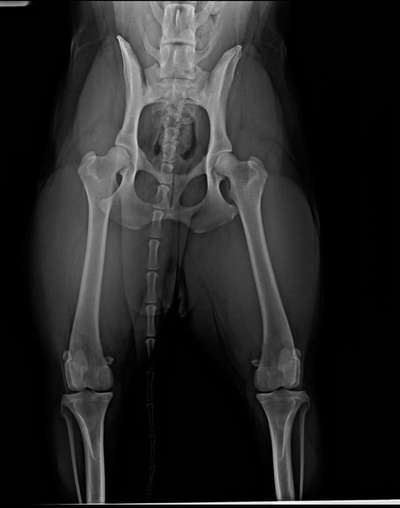

Meine Hündin lahmt seit Monaten . War schon bei drei Tierärzten , die nichts festgestellt haben . Heute war ich auf anraten einer Osteopathin bei einem anderen Tierarzt. Als ich ohm das Röntgenbild zeigte sagte er das es seine Diagnose bestätigt. Er vermutet HD

Leider sind duplizierte Röntgenbilder immer schlechter auszuwerten, als die Orginalen. Feine Zeichnungen, die Hinweise auf Fehlbelastungen oder krankhafte Prozesse geben können, gehen durch die Duplikation verloren. Auf den ersten Blick sieht die Hüfte deines Hundes für mich aber nicht stark verändert aus. Dies heißt aber nicht, dass nicht Anzeichen einer HD vorliegen können.

Um eine HD sicher diagnostizieren zu können, muss eine spezielle Aufnahme des Hüftgelenks erstellt werden. Hierbei ist es wichtig, dass der Hund vollkommen gerade liegt. Anschließend wird mithilfe des sogenannten Norberg-Winkels die Winkelung der Oberschenkelköpfe zur Gelenkspfanne ermittelt. Bei gesunden Hunden sollte dieser Wert über 105° liegen. Zusätzlich werden die Oberflächen der Oberschenkelhalsköpfe sowie der Gelenkspfannen genau beurteilt. Ungleichmäßigkeiten geben Hinweise auf eine vorliegende HD.

Bei der Diagnosestellung wird dein Tierarzt diese Parameter genau beurteilt und somit eine HD bei deinem Hund sicher diagnostiziert haben. Solltest du dennoch unsicher über das Urteil sein kannst du durch eine Zweitmeinung die Diagnose von einem erfahrenen Orthopäden/Orthopädin für Kleintiere absichern lassen. Entsprechende Fachleuchte findest du in Tierkliniken oder spezialisierten Tierarztpraxen.